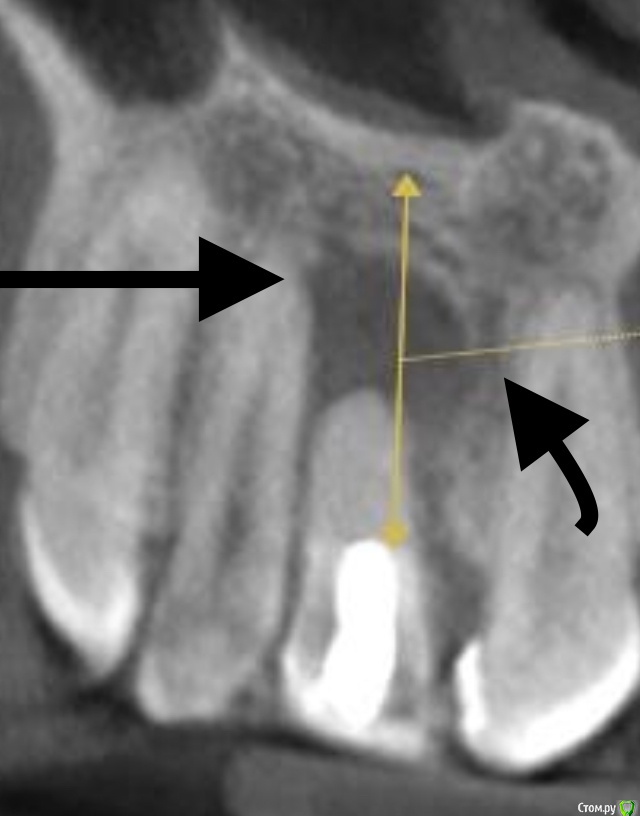

Smileee Опубликовано 17 декабря, 2018 Автор Поделиться Опубликовано 17 декабря, 2018 Имхо отсроченно с консервацией При замерах лучше показать апикальную толщину Вы это имели ввиду? http://b.radikal.ru/b13/1812/de/6462baff108f.jpg Ссылка на комментарий

Irouil Опубликовано 17 декабря, 2018 Поделиться Опубликовано 17 декабря, 2018 Я за одномоментно. Если делать отсроченно ,аугментат может рвануть.Это если только загниет. Вы это имели ввиду?[.jpg]Нет, я про остаточную высоту до дна носа. Торк чтобы предсказуемый был. Ссылка на комментарий

Smileee Опубликовано 17 декабря, 2018 Автор Поделиться Опубликовано 17 декабря, 2018 Это если только загниет.Нет, я про остаточную высоту до дна носа. Торк чтобы предсказуемый был.http://b.radikal.ru/b29/1812/e2/d4482cec4fff.jpg Ссылка на комментарий